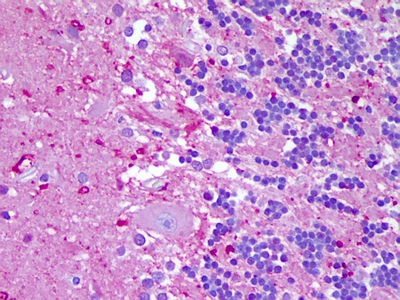

- Anti-NLRP8 antibody IHC of human brain, cerebellum. Immunohistochemistry of formalin-fixed, paraffin-embedded tissue after heat-induced antigen retrieval. Antibody concentration 5 ug/ml.

- Validation comment

- IHC